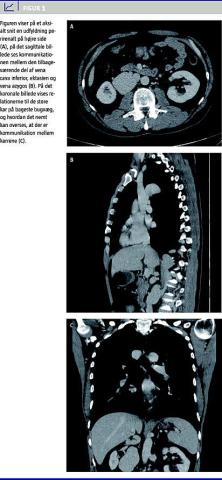

I 2009 fik han jagende fornemmelser i brystet, og han havde en fornemmelse af ikke at kunne få luft. Desuden angav patienten en intermitterende følelse af »lufttomhed" af sekunders varighed. Patienten blev udredt hos kardiologerne, som ikke fandt noget abnormt, hvorefter han blev viderehenvist til Lunge-medicinsk Afdeling. Han havde ingen hoste, havde aldrig røget og var i øvrigt i god almentilstand. Der var normale fund ved objektiv undersøgelse. Biokemisk var der normale forhold og normalt alfaføtoprotein, humant choriongonadotropin og karcinoembryonalt antigen. En udvidet lungefunktionsundersøgelse viste helt normale forhold. Computertomografi (CT) af thorax og abdomen viste overraskende en større RU, der var skarpt afgrænset fra de omkringliggende strukturer (Figur 1 ). Denne tolkedes som et muligt lymfom, idet der i mediastinum også sås flere afrundede strukturer, som kunne minde om glandelkonglomerater. Efterfølgende blev der foretaget CT-vejledt biopsi af området. Med grovnål fik man kun en anelse blod ved biopsi med 1,2 mm-nål uden vævspølse, hvorefter man aspirerede venøst blod fra punkturnålen. Ved et efterfølgende nærstudie af CT'en fandt man fravær af vena cava inferiors hepatiske stykke med fortsættelse af vena cava inferior i vena azygos. RU'en fandtes på overgangen mellem vena cava inferior og vena azygos og måtte betragtes som en større ektatisk kavitet, da den udgjorde kommunikationen mellem de to vener. På baggrund af dette blev karkirurgerne kontaktet. Desværre havde de ingen behandlingstilbud til ham udover fortsættelse af den livslange AK-behandling.